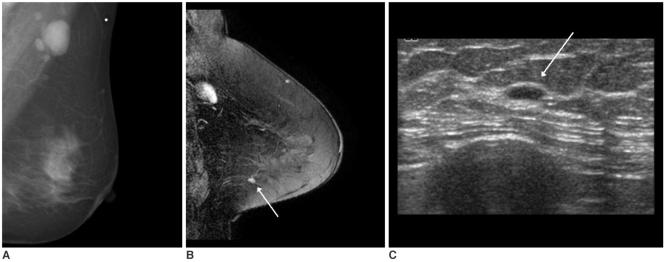

MR imaging detected occult breast carcinoma in 10 of 12 (83%) patients. Two MR-negative patients were free of carcinoma in the ipsilateral breast during their follow-up period (39 and 44 months, respectively). In nine out of 10 patients, the MR-correlated mammography and second-look sonography localized lesions that were not detected on the initial exam. All the non-MR-correlated sonographic abnormalities were benign.

Breast MR imaging can identify otherwise occult breast cancer in patients with metastatic axillary lymph nodes. Localization of the lesions through MR-correlated mammography and second-look sonography is practically feasible in most cases.